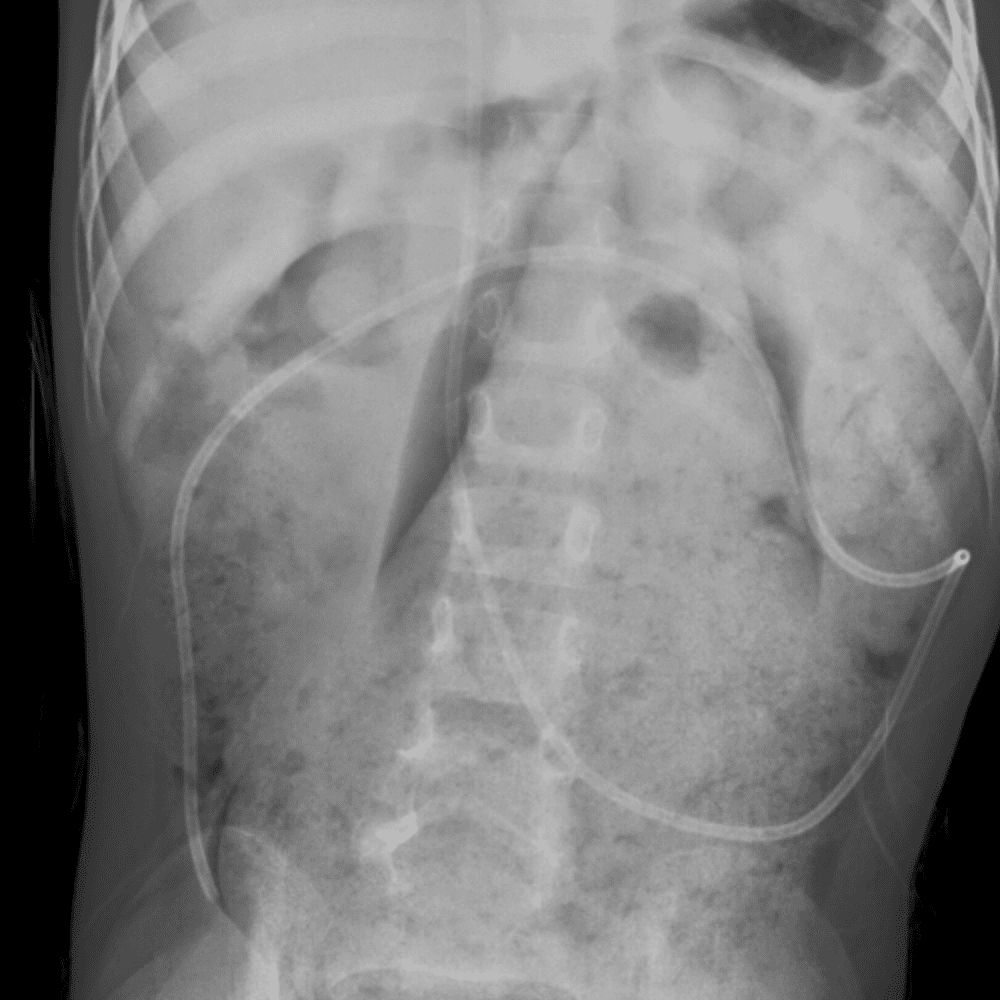

Peds Abdomen

Practice

Simulates call by including subtle or difficult cases and some normals.

30 cases